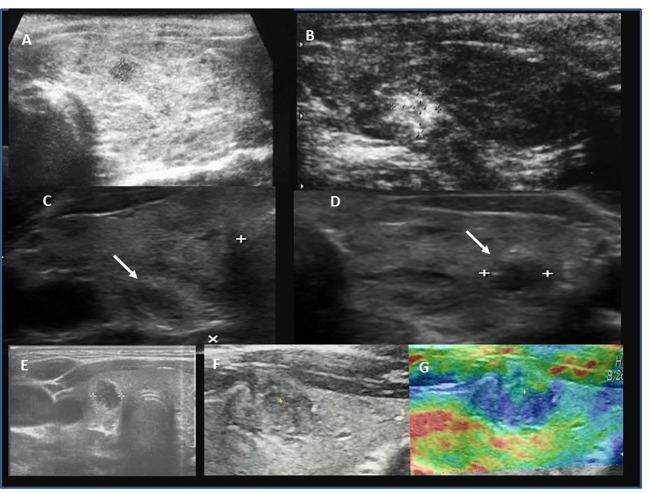

A retrospective analysis of medical records of 90 patients (69; 76.7% females). The mean age at PTC diagnosis was 13.8 years [range 6-18]. All patients were evaluated ultrasonographically before thyroid surgery. Thyroid nodules were categorised using the European Thyroid Imaging Reporting and Data System (EU-TIRADS PL), and cytopathology was assessed using Bethesda criteria. Neck ultrasound results and thyroid and autoimmune status were correlated with histopathological PTC assessment.

回顾性分析 90 例患者(69 例;女性占 76.7%)的病历。PTC 诊断时的平均年龄为 13.8 岁[6-18 岁]。所有患者均在甲状腺手术前进行超声检查。甲状腺结节采用欧洲甲状腺成像报告和数据系统(EU-TIRADS PL)进行分类,细针穿刺细胞学检查采用 Bethesda 标准评估。颈超声结果和甲状腺及自身免疫状态与组织病理学 PTC 评估相关。

In paediatric patients the natural course of PTC may be less aggressive in adolescent patients than in younger children (especially < 10 years of age). We suggest that pre-operative evaluation of paediatric patients with thyroid nodules could include apart from assessment of thyroid hormones, evaluation of TPOAb, TgAb, and TRAb together with comprehensive neck ultrasonography.

结论